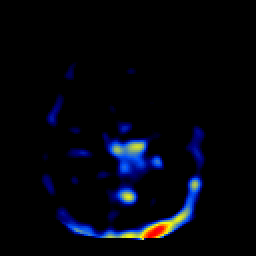

SPECT TL Study #2 -- Slice #34

[Home][Help][Clinical][Tour 1][Tour 2][Tour 3] Slice 34